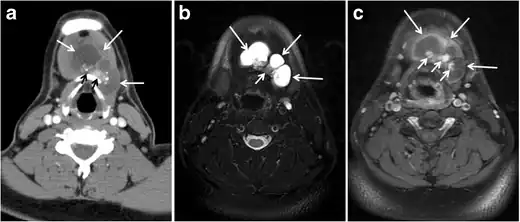

Thyroid lymphoma represents about 5% of thyroid malignancies. Non-Hodgkin's lymphoma is the most common type and can be secondary to generalized lymphoma or a primary tumour. Primary thyroid lymphoma usually pre-exists with Hashimoto's thyroiditis. On CT scans with and without contrast, lymphomas tend to have low attenuation values. Thyroid lymphomas have a variable appearance and mostly manifest as a solitary mass (80%). They may also manifest as multiple nodules (15% to 20%) or as a bulky mass replacing the entire gland with extra-thyroid extension (Figs. 11 and and12).12). The presence of cervical lymphadenopathy supports such a diagnosis. Although it is uncommon, tumour necrosis has been reported.[1]

Goiter

A goiter is an abnormal thyroid gland proliferation that manifests as multi-nodular, uni-nodular, or non-nodular diffuse glandular enlargement. A goiter is formed of solid matrix, colloid cysts, blood products, calcification, and fibrosis, and this heterogeneity may lead to variable appearances on a CT scan (Figs. 13, 1414 and and15)15). The US is more sensitive in evaluating thyroid nodules within a goiter; however, a symptomatic goiter may require surgical treatment with total thyroidectomy, and in this case CT plays an additional role in preoperative evaluation. Specific aspects for examination on a CT scan during the preoperative evaluation for goiter include extension, mass effect, and suspicious features of malignancy.[1]

Malignancy can coexist within the goiter and a CT scan may give a clue if there are abnormal cervical lymph nodes and/or signs of invasion. Retrosternal extension (Fig. 15) could affect the surgical approach, as a lower extent may require a partial or total sternotomy to facilitate complete resection. Therefore, the distance of the retrosternal extent from the sternal notch should be measured on a sagittal image.[1]

The interpreting radiologist should describe the mass effect, detailing its degree and direction of displacement of central structures, including the trachea, oesophagus, larynx, and pharynx. Attention should be directed to the upper extent of the goiter and structures immediately surrounding the thyroid gland, including the neuro-vascular structures, retropharyngeal space, and pre-vertebral space. The reporting radiologist should evaluate the vocal cords for symmetry and signs of vocal cord palsy.[1]